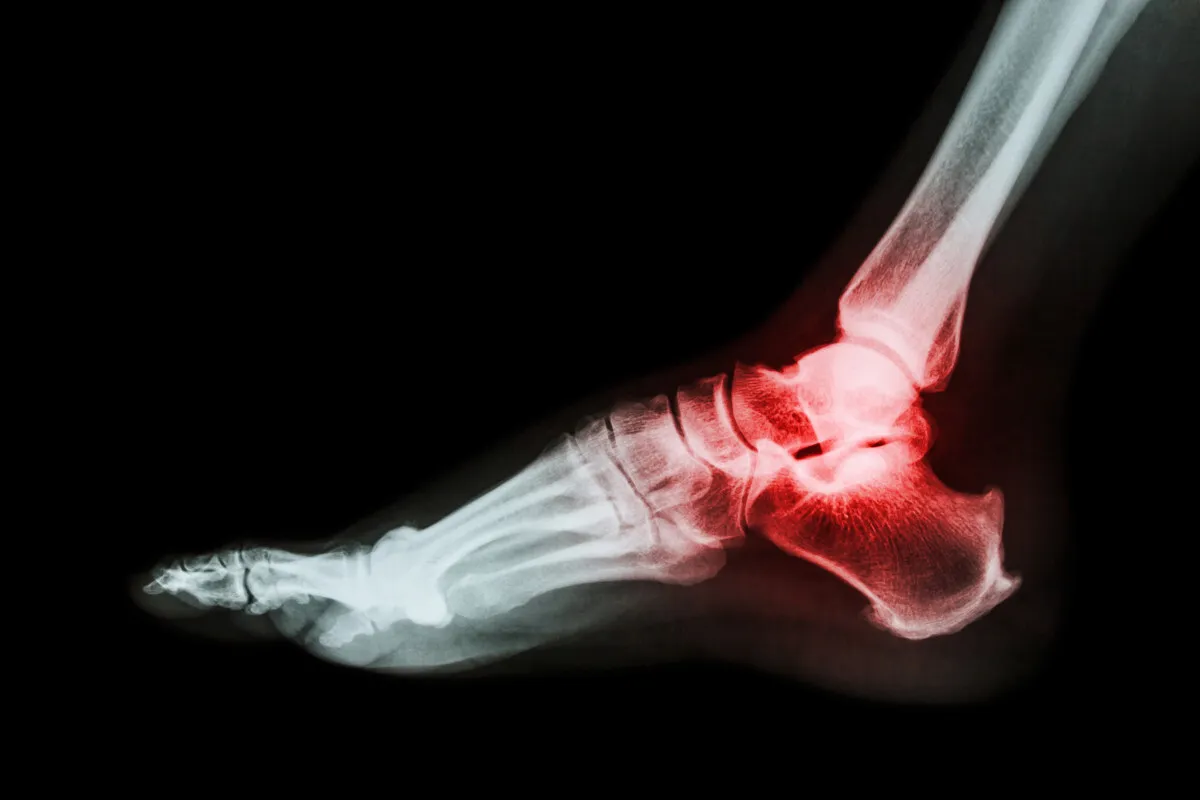

Złamanie kości piętowej to jeden z poważniejszych urazów stopy, który znacząco wpływa na codzienne funkcjonowanie. Proces powrotu do pełnej sprawności po takim złamaniu jest często długi i wymaga ogromnej cierpliwości oraz konsekwentnej pracy. W tym artykule, jako Apolonia Sobczak, postaram się przedstawić realistyczne ramy czasowe i szczegółowe etapy rehabilitacji, abyś wiedział, czego możesz się spodziewać na swojej drodze do odzyskania zdrowia.

Powrót do sprawności po złamaniu kości piętowej co musisz wiedzieć o długości i etapach rehabilitacji?